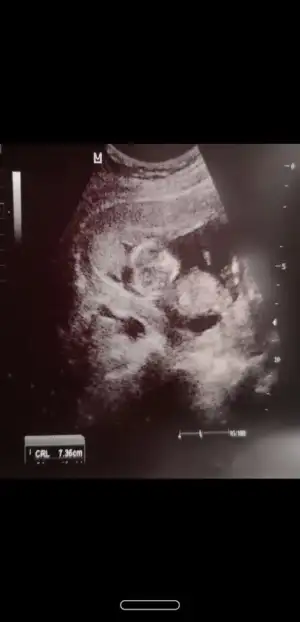

Canım bi de bu var ,ben de bugün başka doktora gittim direkt erkek dedi emin mısınız dedim sanki pipi gördüm dedi ama bir ay sonra netlesir dedi :)

Kız tabiki burda ama sonraki büyük haftada nub olmaz ☺️ demekki kordon gelmiş yoksa diğeri net bariz kız nubu 🙈